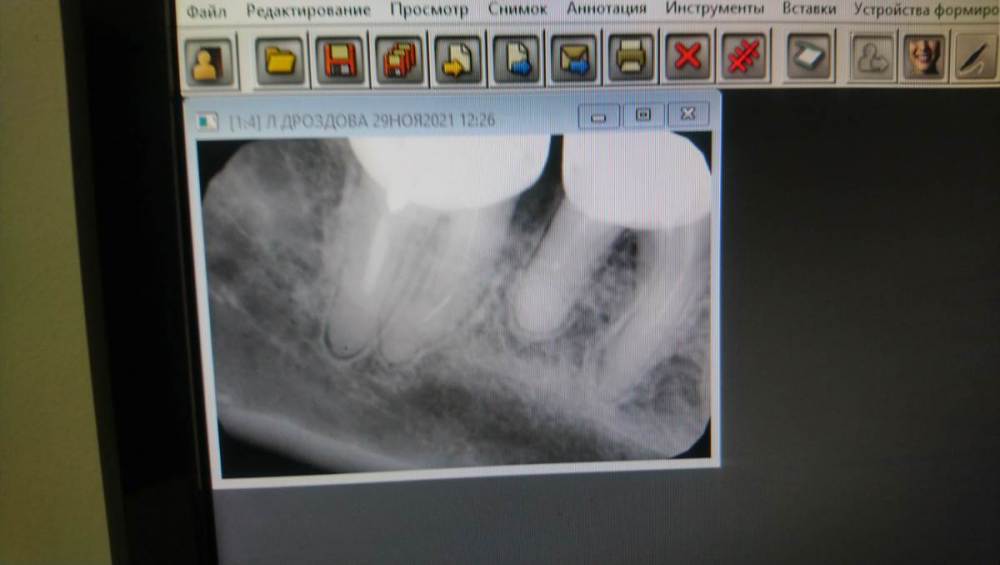

moskva130178@yandex.ru Опубликовано 30 ноября, 2021 Поделиться Опубликовано 30 ноября, 2021 (изменено) Подскажите, пожалуйста, на днях болел зуб под коронкой, вечером и ночью болел, а на следующий день вечером перестал болеть без таблеток. Болел зуб, с температурой 37,который на снимке поменьше, справа налево, второй. Сделала снимок. Что сказал врач, что в двух зубах инструменты. Это так? Сильное воспаление. Подскажите, пожалуйста, если оставить как есть, не снимать коронки, может ли зуб не болеть? И в 2 зубах инструменты? Который зуб болел, лечили год назад. А рядом который зуб, лет 6 назад.Верхний снимок сейчас, а нижний 2010, есть ли изменения за 11лет? Болел зуб, который рядом Изменено 30 ноября, 2021 пользователем moskva130178@yandex.ru Добавилафайл Ссылка на комментарий

St. Опубликовано 2 декабря, 2021 Поделиться Опубликовано 2 декабря, 2021 Воспаление небольшое, по сравнению 2 снимков больше не стало. сломанные инструменты есть, но нужно понимать что даже при перелечивании не всегда получается их достать и перелечить каналы. Может болеть, может не болеть, тут как повезет. Как вариант, если не собираетесь менять коронки на этих зубах то можно наблюдать. Если начнут беспокоить или станет вопрос замены коронок на новые, то станет и вопрос перелечивания Ссылка на комментарий